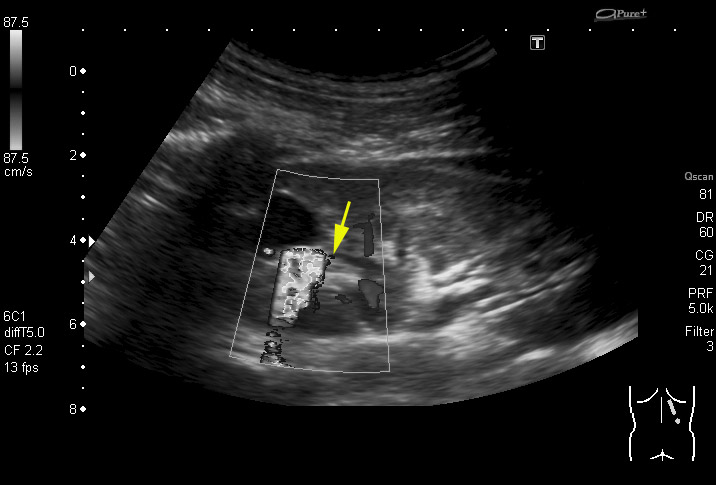

Артефакт цветного твинклинга

Ролик с ЦДК

Для меня самое интересное находится здесь:

Нет, меня интересует "или".dok69 писал(а):Вас занимает артефакт- "мерцания" или ...?